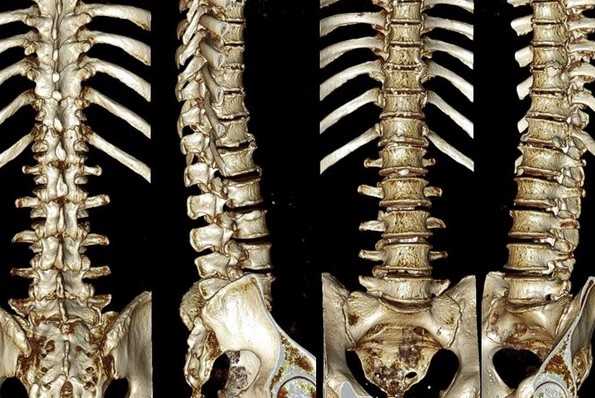

Сколиоз позвоночника на снимках КТ